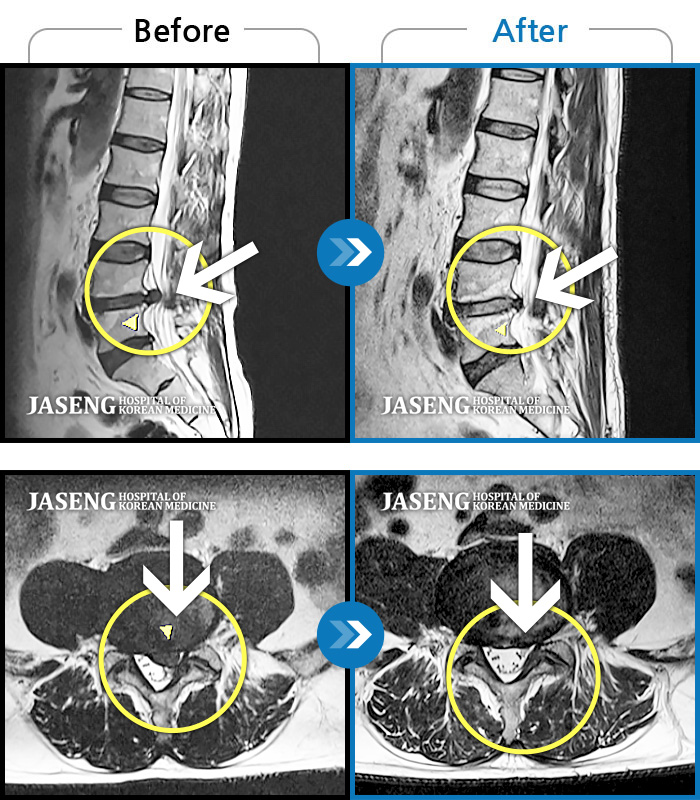

MRI 치료사례

좌측 허리 통증, 좌측 하지 뒤쪽으로 저림 증상